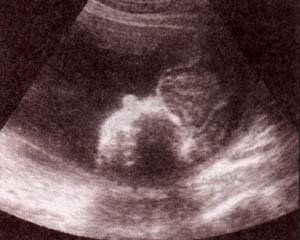

fig. 60. – (a). excencefalia. 18 semanas. se observa tejido cerebral flotando libremente en ausencia de calota. asociado un defecto lumbosacro. |